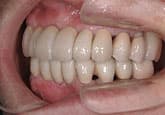

MJさん(20歳・女性)

初診時:左上の歯肉が痛い